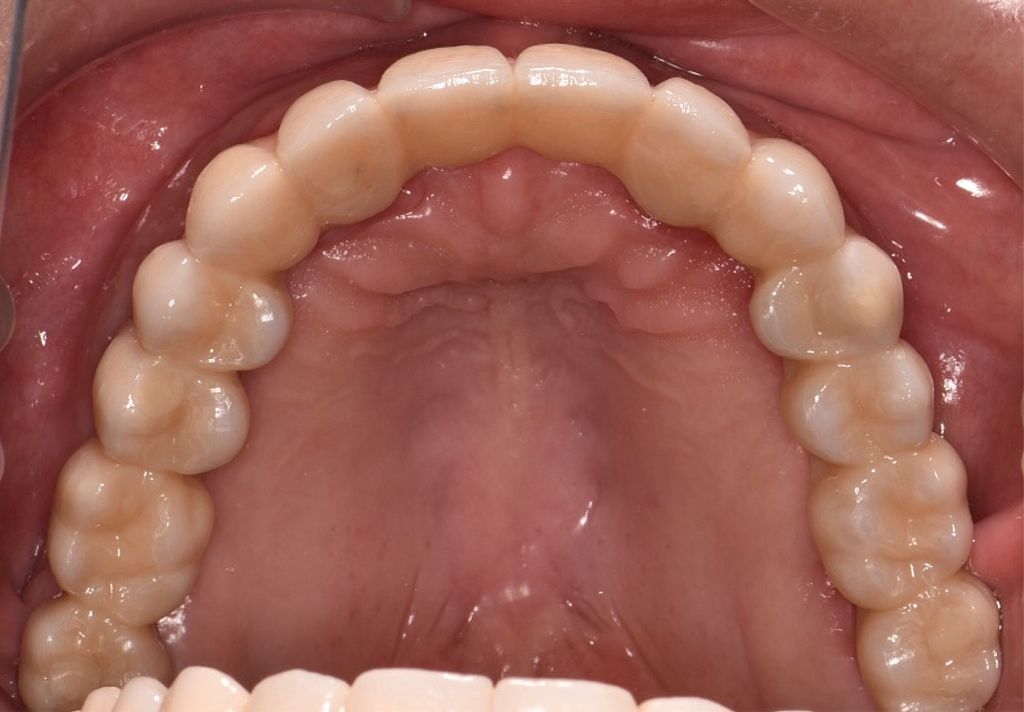

Zirconia Implants

After